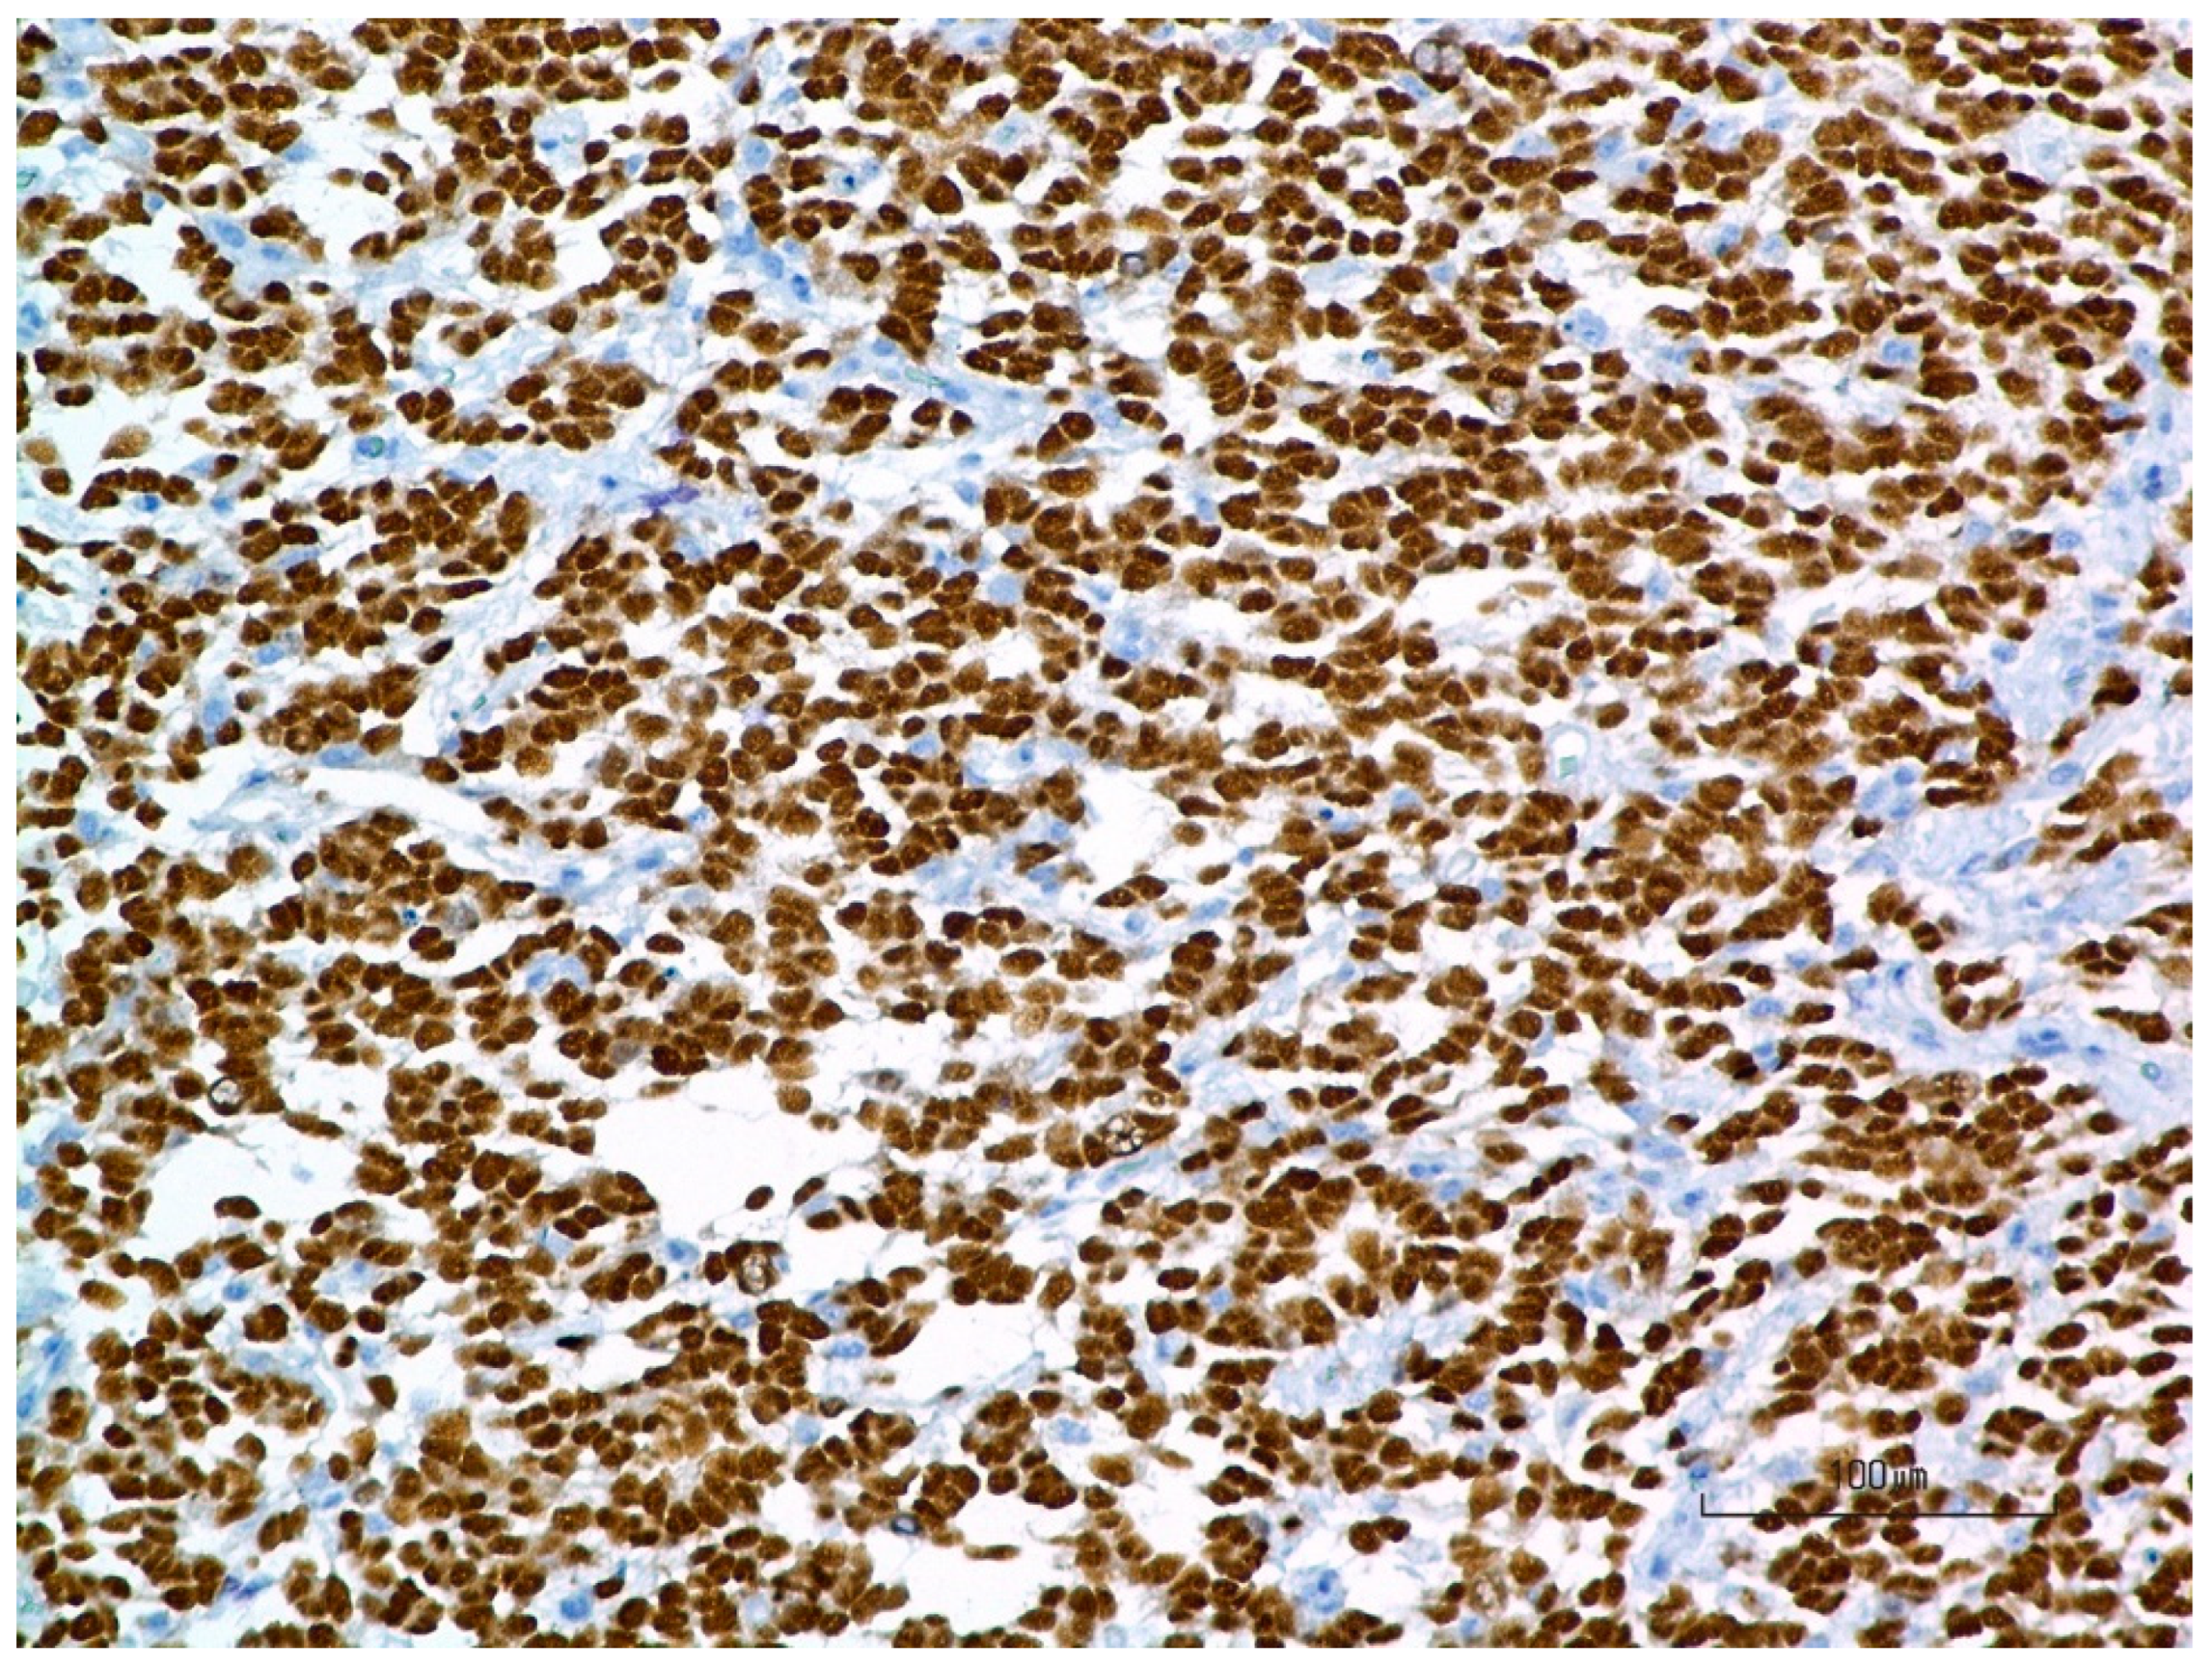

3.4. Pathology